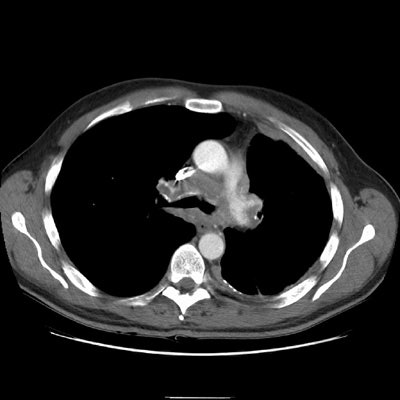

The right upper lobe pulmonary vein can be seen just lateral and slightly posterior to the SVC. It is markedly narrowed and distorted by the mediastinal infiltrative soft tissue abnormality. No left upper lobe pulmonary vein is identified. The left pulmonary artery structures are narrowed and irregular.